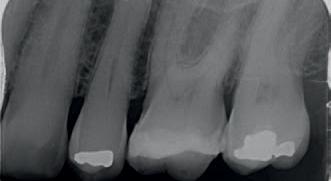

In 2024, the patient presented again with pain in tooth 26. He reported the tooth was very sensitive to cold, with the pain lasting several minutes. He also reported that the tooth had ached spontaneously at times. On examination, the tooth reacted very strongly to cold, which lasted for almost one minute. The tooth was also slightly tender to percussion. The composite resin restoration appeared sound (Fig. 2). A PA radiograph (Fig. 3) revealed no PARL, but the pulp chamber was reduced in size when compared to a previous bite-wing radiograph.

Fig. 3: PA radiograph.